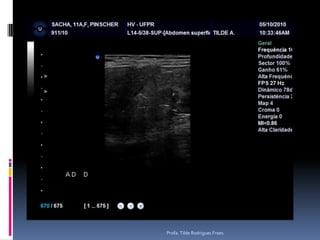

Animal: Sacha, canino, fêmea, 11 anosAvaliação – suspeita de HiperadrenocorticismoProfa. Tilde Rodrigues Froes

Animal: Sacha, canino,fêmea, 11 anosAvaliação – suspeita de HiperadrenocorticismoProfa. Tilde Rodrigues Froes